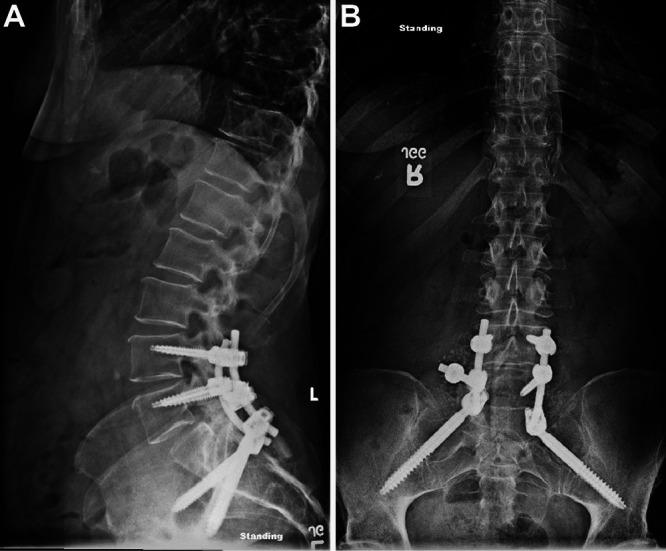

In this case, a 54-year-old woman with history of systemic scleroderma presented with 10 months of progressive left lumbosacral pain. Imaging revealed an expansile, 4 × 7-cm, well-circumscribed mass in the lumbosacral spine with L5-S1 neuroforaminal compression. Because intractable pain and computed tomography (CT)-guided needle biopsy did not entirely rule out malignancy, operative management was pursued. The patient underwent L4-S2 laminectomies, left L5-S1 facetectomy, L5 and S1 pediculectomies, and en bloc resection, performed under stereotactic CT-guided intraoperative navigation. Subsequently, instrumented fusion was performed with L4 and L5 pedicle screws and S2 alar-iliac screws. Pathological examination was consistent with tumoral calcinosis, with multiple nodules of amorphous basophilic granular calcified material lined by histiocytes. There was no evidence of recurrence or neurological deficits at 5-month follow-up.

在本病例中,一名有系统性硬化症病史的54岁女性出现了10个月的进行性左腰骶部疼痛。影像学检查显示腰骶部有一个4×7厘米、边界清晰的膨胀性肿块,压迫L5 - S1神经孔。由于顽固性疼痛以及计算机断层扫描(CT)引导下的穿刺活检未能完全排除恶性肿瘤,因此采取了手术治疗。患者在立体定向CT引导下的术中导航下行L4 - S2椎板切除术、左侧L5 - S1小关节切除术、L5和S1椎弓根切除术以及整块切除术。随后,使用L4和L5椎弓根螺钉以及S2翼状髂骨螺钉进行器械融合。病理检查结果与肿瘤性钙化一致,有多个由组织细胞衬里的无定形嗜碱性颗粒状钙化物质结节。在5个月的随访中,没有复发或神经功能缺损的证据。